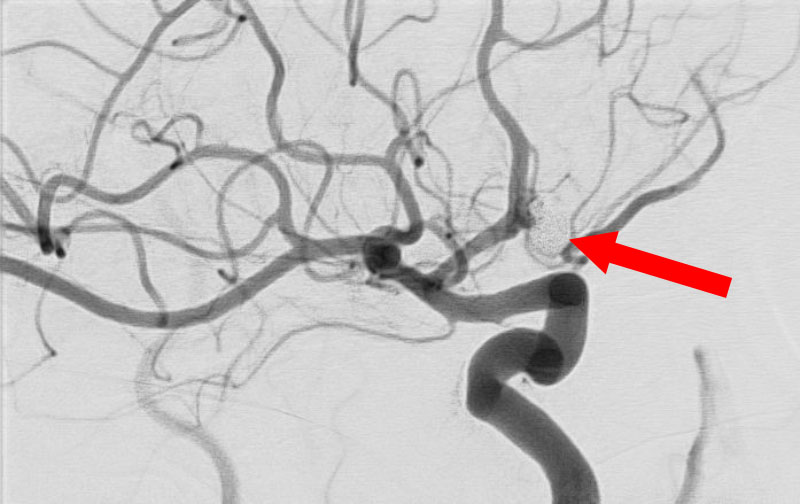

'25年11月

くも膜下出血

右内頚動脈後交通動脈

分岐部動脈瘤破裂

60代

救急外来

No.1593 手術前

No.1593 手術中

No.1593 手術後